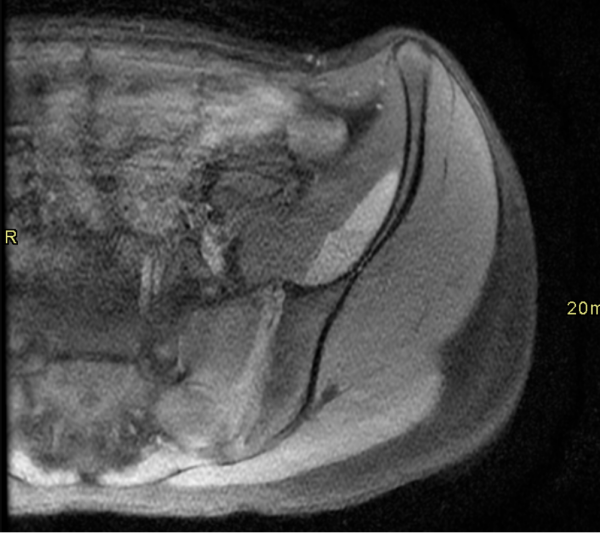

Secuencias de pelvis axial, T1 FSE, sin (Imagen 4) y con contraste (Imagen 5). La lesión presenta señal alta, levemente heterogénea, con nivel líquido-líquido. No demuestra realce significativo con el contraste endovenoso.